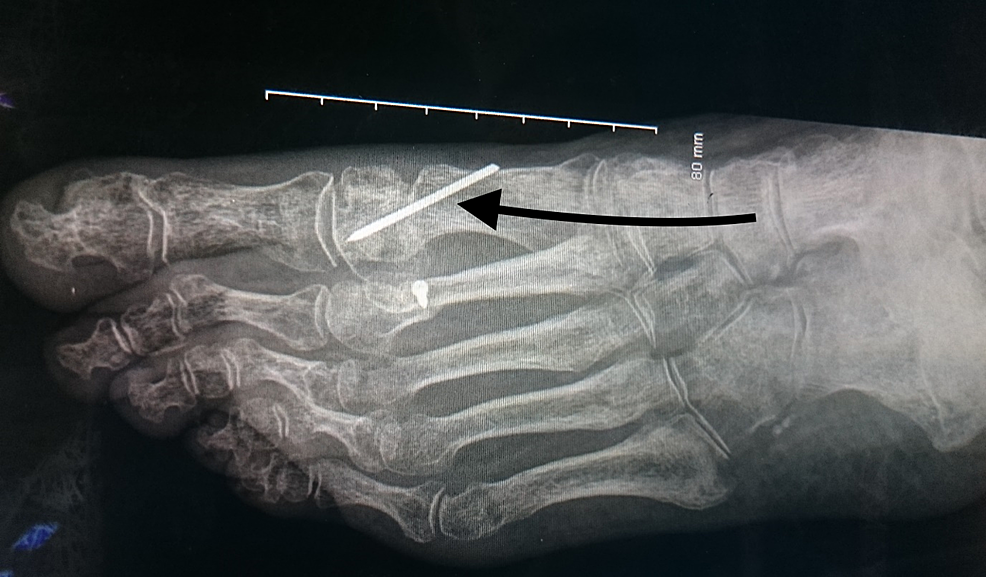

CRUSH INJURY FOOT MULTIPLE METATARSAL FRACTURE DEBRIDMENT , KWIRE Metatarsal Fracture K-Wire Fixation Metatarsal fractures pose significant challenges in orthopedic practice, necessitating effective treatment methods to ensure optimal. Intramedullary implants can be inserted retrograde, either directly through the metatarsal head or from the tip of the phalanx. Standard open fracture management, with initial irrigation and debridement with appropriate antibiotic coverage, is indicated. Our results demonstrate that k wire intramedullary nailing regardless of the. Metatarsal Fracture K-Wire Fixation.